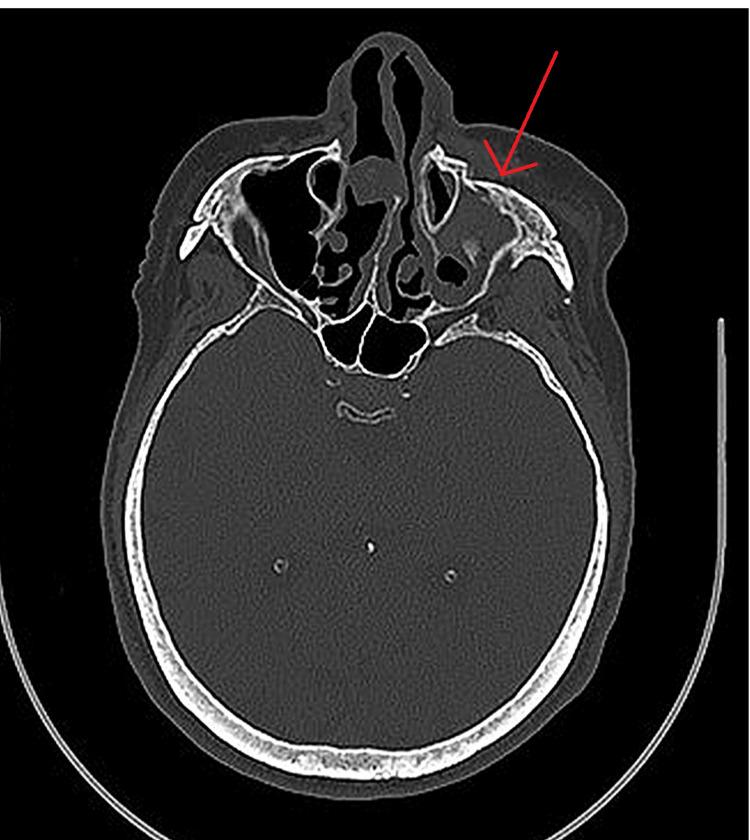

Facial trauma can cause skin wounds with uneven and discoloured edges that require healing by secondary intention. These wounds often produce excess collagen fibres, leading to fibrosis and hypertrophic scars that can cause discomfort and negatively impact the patient's quality of life. A man suffered facial trauma due to a motor vehicle accident, resulting in a fracture of the left zygomatic-maxillary complex. He underwent surgery to fix the fracture and reconstruct his eyelid but developed a hypertrophic scar during recovery that caused eye dryness and discomfort. To treat the scar, Dermatix silicone gel (SG) (Viatris, Canonsburg, PA) was applied twice a day. After two months of treatment, the scar had improved significantly, and the patient's eyelid function had also improved. This case describes the use of Dermatix SG to treat a patient with a traumatic hypertrophic scar of the eyelid associated with eyelid malposition. Silicone gel is a non-invasive treatment for scars and has been shown to be effective in reducing scar elevation and erythema. However, there is a gap in the literature regarding the routine use of SG to preserve functionality and aesthetics in traumatic hypertrophic scars of complex anatomical structures. Further studies are needed to understand the principles of using SG for these types of scars to improve functional and aesthetic outcomes. Applying Dermatix SG twice a day for 60 days corrected a patient's functional and aesthetic issues. More studies should be conducted to investigate the product's effectiveness further.

面部创伤可导致皮肤伤口边缘参差不齐且颜色不均,需要二期愈合。这些伤口通常会产生过多的胶原纤维,导致纤维化和肥厚性瘢痕,从而引起不适并对患者的生活质量产生负面影响。一名男子因机动车事故遭受面部创伤,导致左侧颧骨-上颌复合体骨折。他接受了修复骨折和重建眼睑的手术,但在恢复过程中出现了肥厚性瘢痕,导致眼睛干涩和不适。为了治疗瘢痕,每天两次涂抹倍舒痕硅凝胶(SG)(维奥制药公司,宾夕法尼亚州卡农斯堡)。经过两个月的治疗,瘢痕明显改善,患者的眼睑功能也有所改善。本病例描述了使用倍舒痕硅凝胶治疗一名伴有眼睑错位的外伤性眼睑肥厚性瘢痕患者的情况。硅凝胶是一种非侵入性的瘢痕治疗方法,已被证明在减少瘢痕隆起和红斑方面有效。然而,关于常规使用硅凝胶来保持复杂解剖结构的外伤性肥厚性瘢痕的功能和美观方面,文献中存在空白。需要进一步研究以了解使用硅凝胶治疗这类瘢痕的原理,从而改善功能和美观效果。每天两次涂抹倍舒痕硅凝胶,持续60天,纠正了患者的功能和美观问题。应该进行更多研究以进一步调查该产品的有效性。